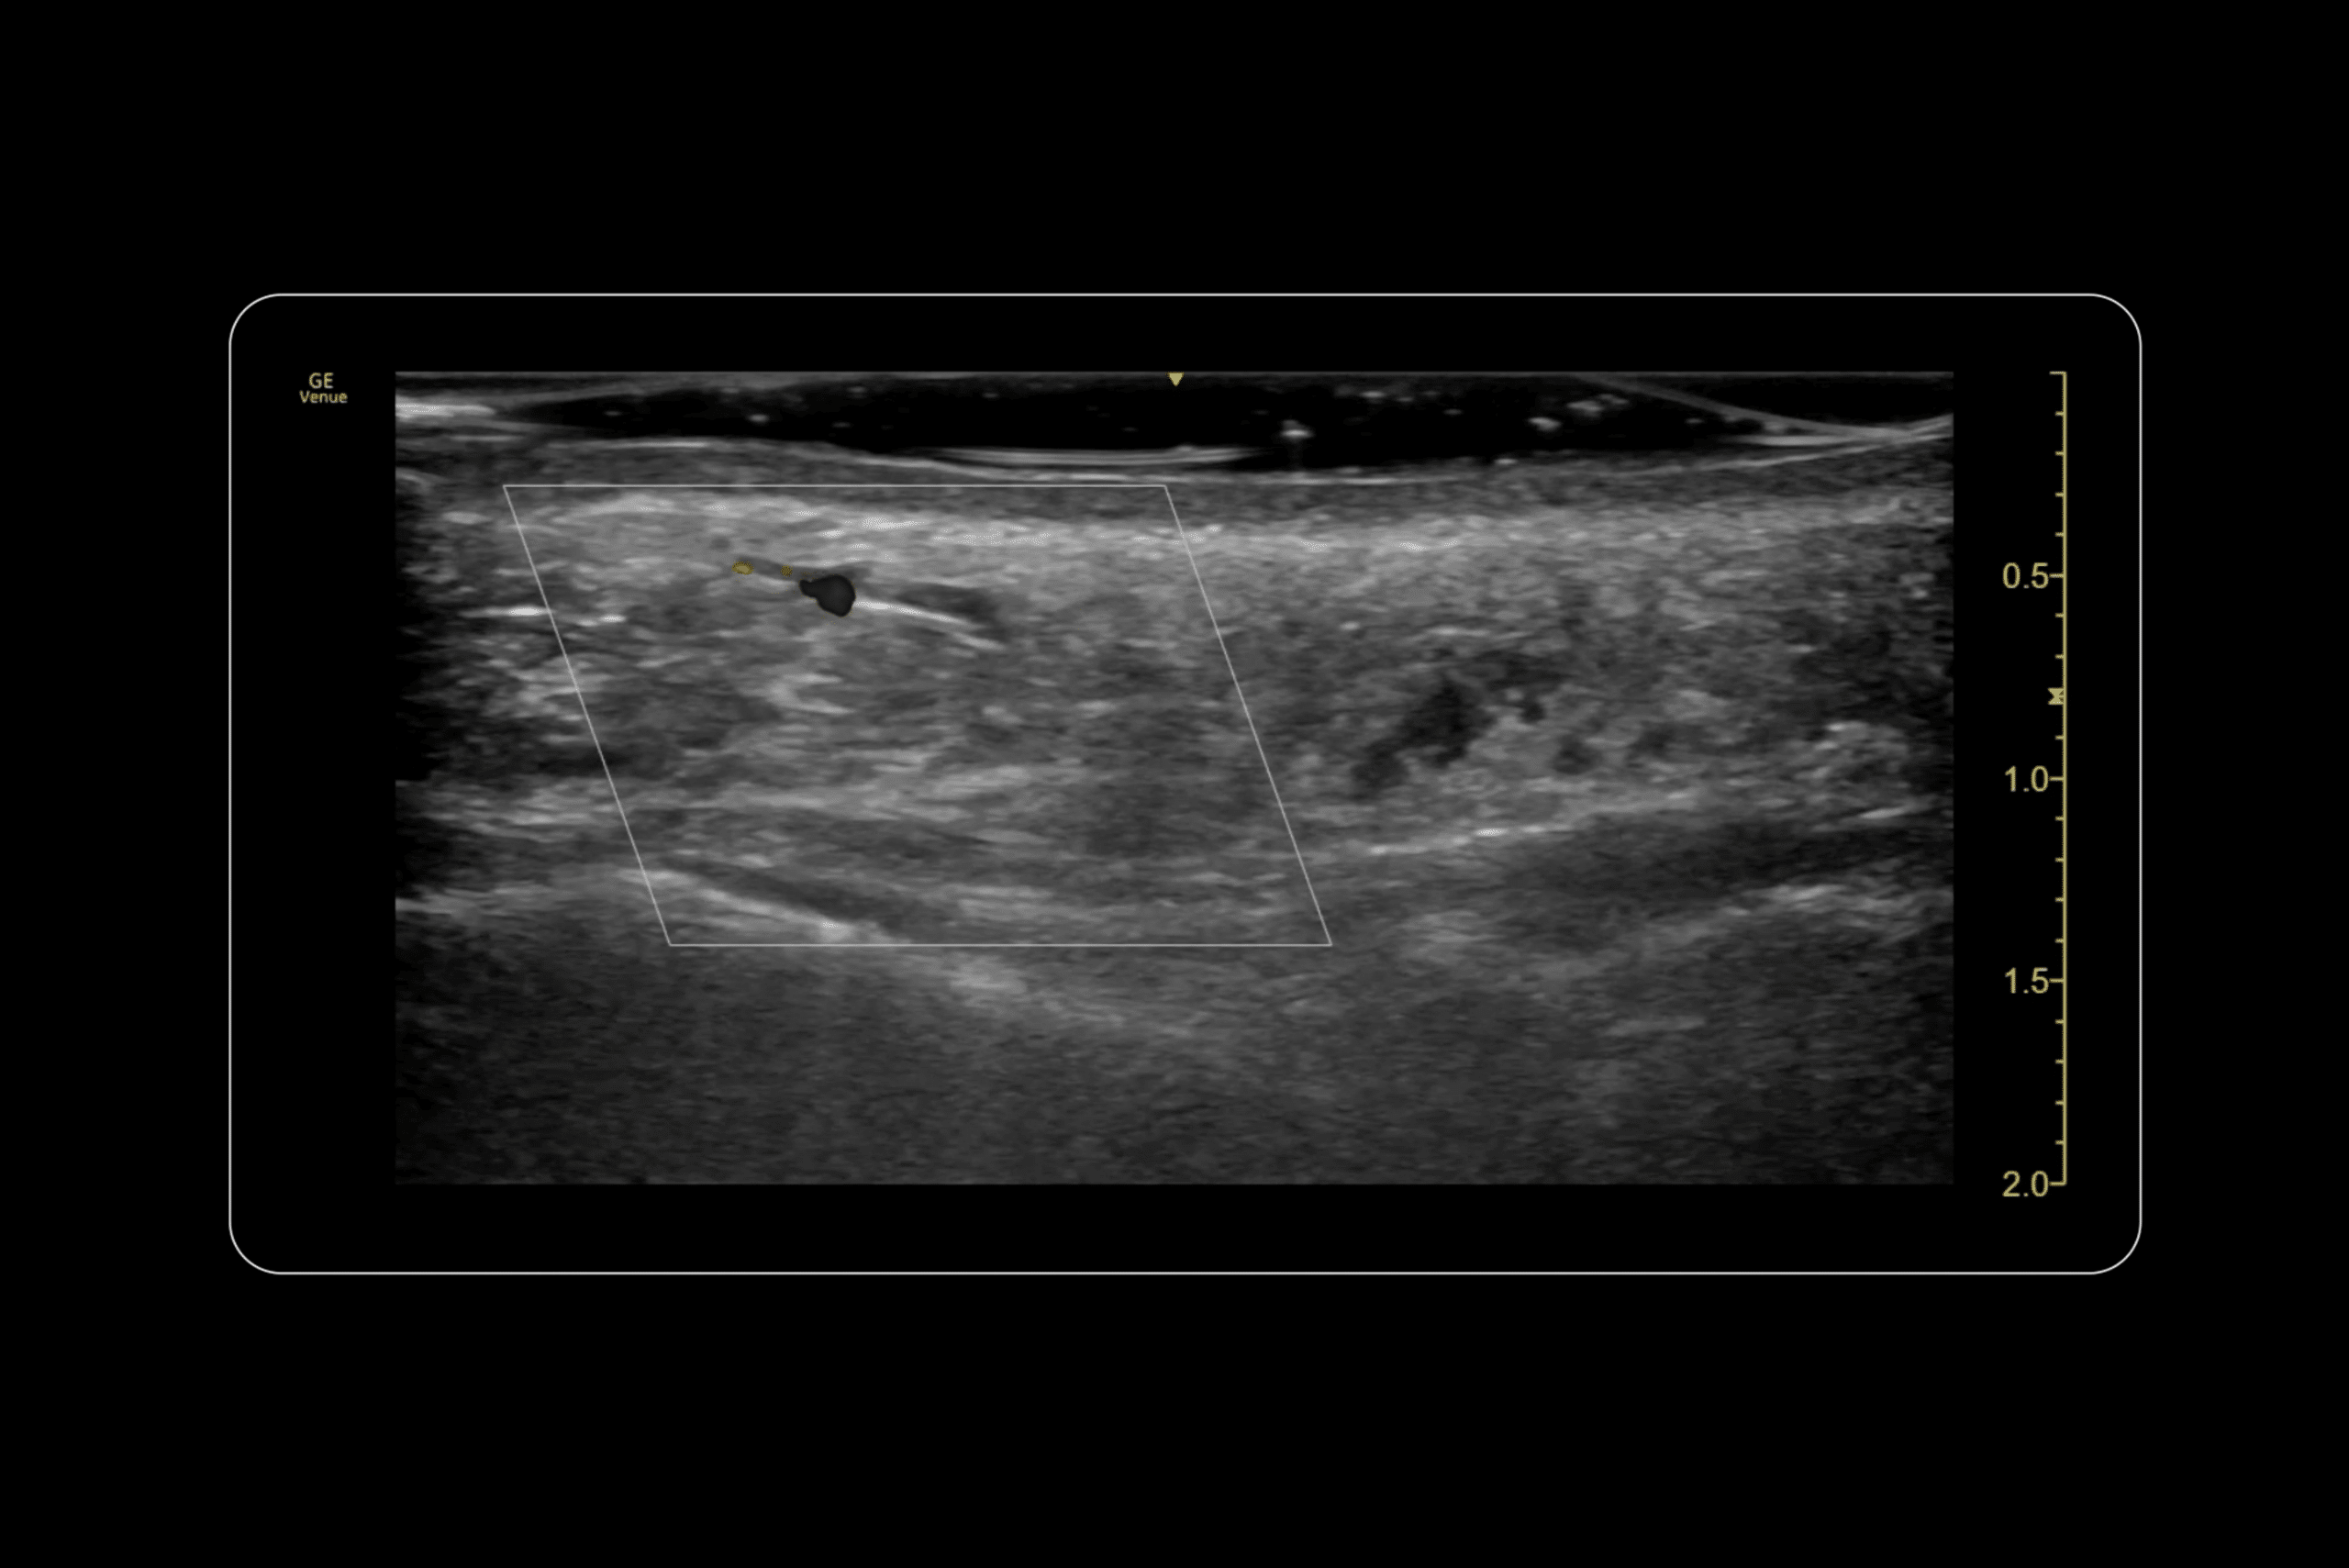

Dr MJ demonstrates this precision in our Advanced Facial Ultrasound course, using ultrasound guidance to identify and dissolve specific filler deposits that are causing problems. The technique involves visualising the exact location of unwanted filler, which appears hypoechoic (dark) on ultrasound with posterior acoustic enhancement, confirming its hyaluronic acid composition.

The correction process requires understanding not just where the filler is but why it’s causing problems. Sometimes the tissue is simple overfilling. Other times, filler may be irritating nearby blood vessels, causing hypervascularity and the clinical symptoms patients describe as puffiness and oedema.

Using ultrasound guidance allows practitioners to navigate safely around blood vessels while targeting problematic filler deposits with small amounts of hyaluronidase. Even minimal amounts of the dissolving enzyme can disrupt HA deposits, with immediate visualisation of the structural changes on ultrasound.